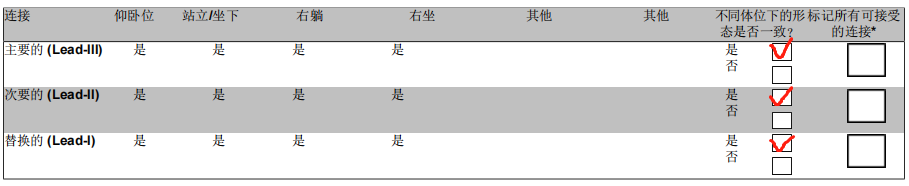

术前筛查报告